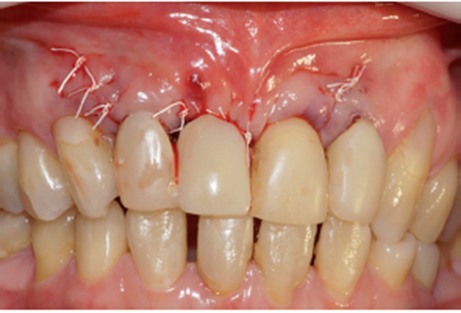

O procedimento cirúrgico foi iniciado através de uma anestesia infiltrativa com articaína 4%. Foram realizadas incisões relaxantes (Figura 4) para expor o leito cirúrgico e, consequentemente, a lesão periapical (Figura 5). Após o deslocamento do retalho, foi realizada a exodontia de forma atraumática (Figura 6) e na sequência, foi feita a curetagem do alvéolo removendo todo o tecido de granulação (Figura 7). Uma vez realizada a toalete do leito cirúrgico (Figuras 8 e 9), o implante Cone Morse Due Cone de 3.5 X 13 mm (Implacil De Bortoli) foi instalado seguindo o melhor posicionamento dentro do rebordo residual, conforme planejado (Figuras 10 e 11). Em sequência, foi realizada a instalação do Cover Screw (Figura 12) e o preenchimento do defeito ósseo com biomaterial (Bio-Oss 0,25), conforme figuras 13 e 14). O fechamento foi realizado com membrana de PTFE-d (Cytoplast TXT–200, Osteogenics – Lubbock TX, EUA), customizada para ser adaptada sobre o defeito ósseo, estendendo-se de 3 a 5 mm da margem do defeito ósseo e intencionalmente exposta (Figura 15). A sutura foi realizada com fio de PTFE (Cytoplast), como podemos observar na figura 16, e instalado um provisório adesivo na região (Figura 17).